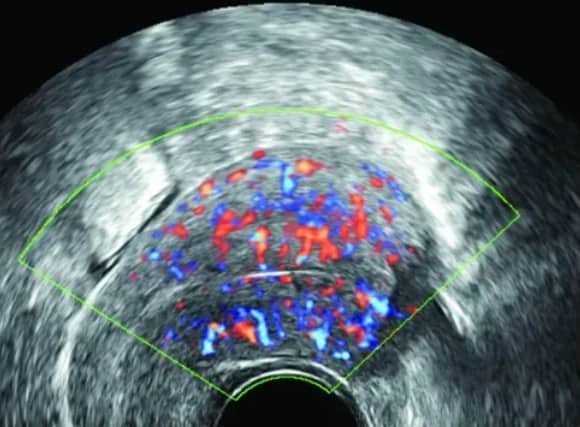

当患者卵巢功能异常时,会影响卵泡刺激素的分泌功能,进而出现卵泡刺激素低下的症状,会导致患者出现的症状,严重时可能会影响妊娠。卵泡刺激素低是由内分泌失调引起的。这种激素由脑垂体分泌,属于生殖系统,在血液中变化很大。有些女性性生活不规律,长期熬夜,工作日程也很紊乱。时间长了会影响内分泌,很可能导致内分泌紊乱,子宫和卵巢也会受到内分泌影响,神经功能紊乱,导致卵泡刺激素稍低或偏高。

如果卵泡刺激素减少,可能是卵巢功能障碍、综合征或垂体异常引起的。不管哪种情况对怀孕有影响,都要明确原因再治疗。如果女性卵泡刺激素高,卵巢就不能正常、充分地受到刺激,进行正常的激素分泌和卵子生成,就会导致女性无法正常排卵,从而引起内分泌异常。卵巢分泌的雌激素不足会导致不孕。